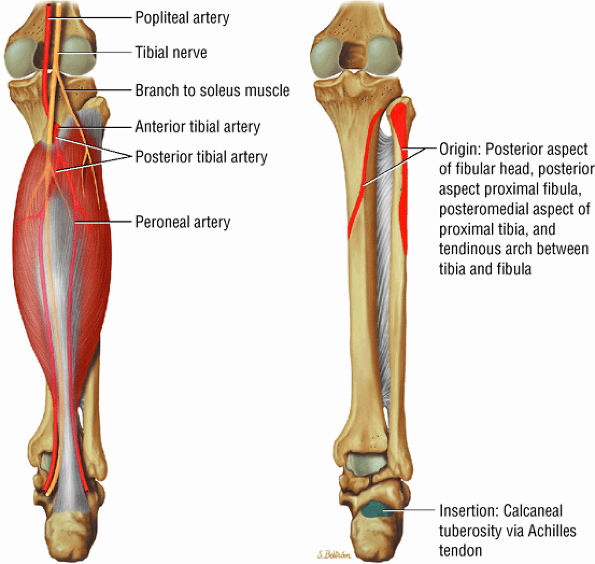

The posterior muscles of the leg include a superficial group and deep group. The superficial group is represented by the gastrocnemius (Fig. 5.6), the soleus (Fig. 5.7), and plantaris (Fig. 5.8).

FIGURE 5.7 ● SOLEUS The gastrocnemius and the soleus muscles function in plantarflexion of the foot. The soleus consists primarily of type I or slow-twitch oxidative fibers and rapidly develops disuse atrophy in response to immobilization.